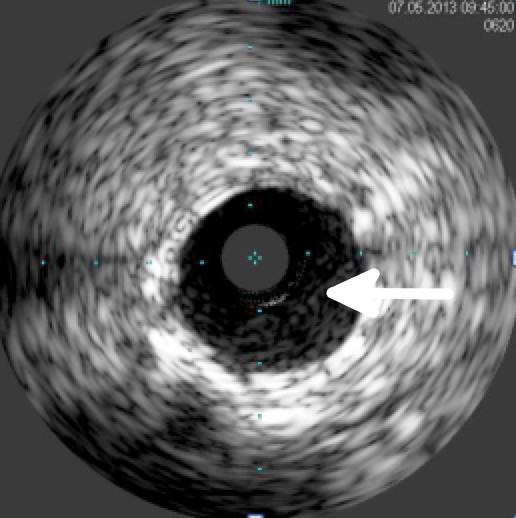

Gefäß nach Implantation

Der IVUS wurde in der interventionellen Kardiologie besonders bei der Planung und Durchführung komplexer Interventionen, als auch in der Verlaufskontrolle nach Stentimplantation als geeignete Methode etabliert.

Der intravaskuläre Ultraschall wird in der Medizinischen Klinik I am Universitätsklinikum Giessen routinemäßig eingesetzt, um im Besonderen komplexe Bifurkationsstenosen, Stenosen des Hauptstamms, oder Stenosen an mehreren Koronararterien zu beurteilen. Dies erlaubt eine für jeden Patienten optimal zugeschnittene Therapie.